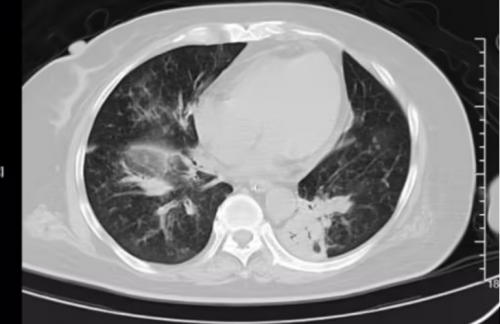

2025.11.21

胸部影像学

患者,女60岁,因咳嗽气促发热1天余,并伴有一般体力活动时气促不适,自觉发热,有胸闷不适,查胸部CT示双肺多发斑片状高密度影,血气分析提示I型呼吸衰竭,于2025年11月21日诊断为重症肺炎I型呼吸衰竭ARDS收入我科。

胸部+上腹部CT:1、两肺感染,左肺下叶支气管内粘液栓,建议治疗后复查,2、两肺多发结节(LU-RADS 2、3类),间隔3-6个月随诊。3、左心室增大,主动脉硬化,主动脉瓣膜钙化。4、甲状腺左叶钙化灶,调结合超声。5、左肾积气,请结合临床,建议进一步检查。6、双肾小结石。7、升结肠肠腔内软组织密度影:肠内容物?占位?建议复查或者内径检查。